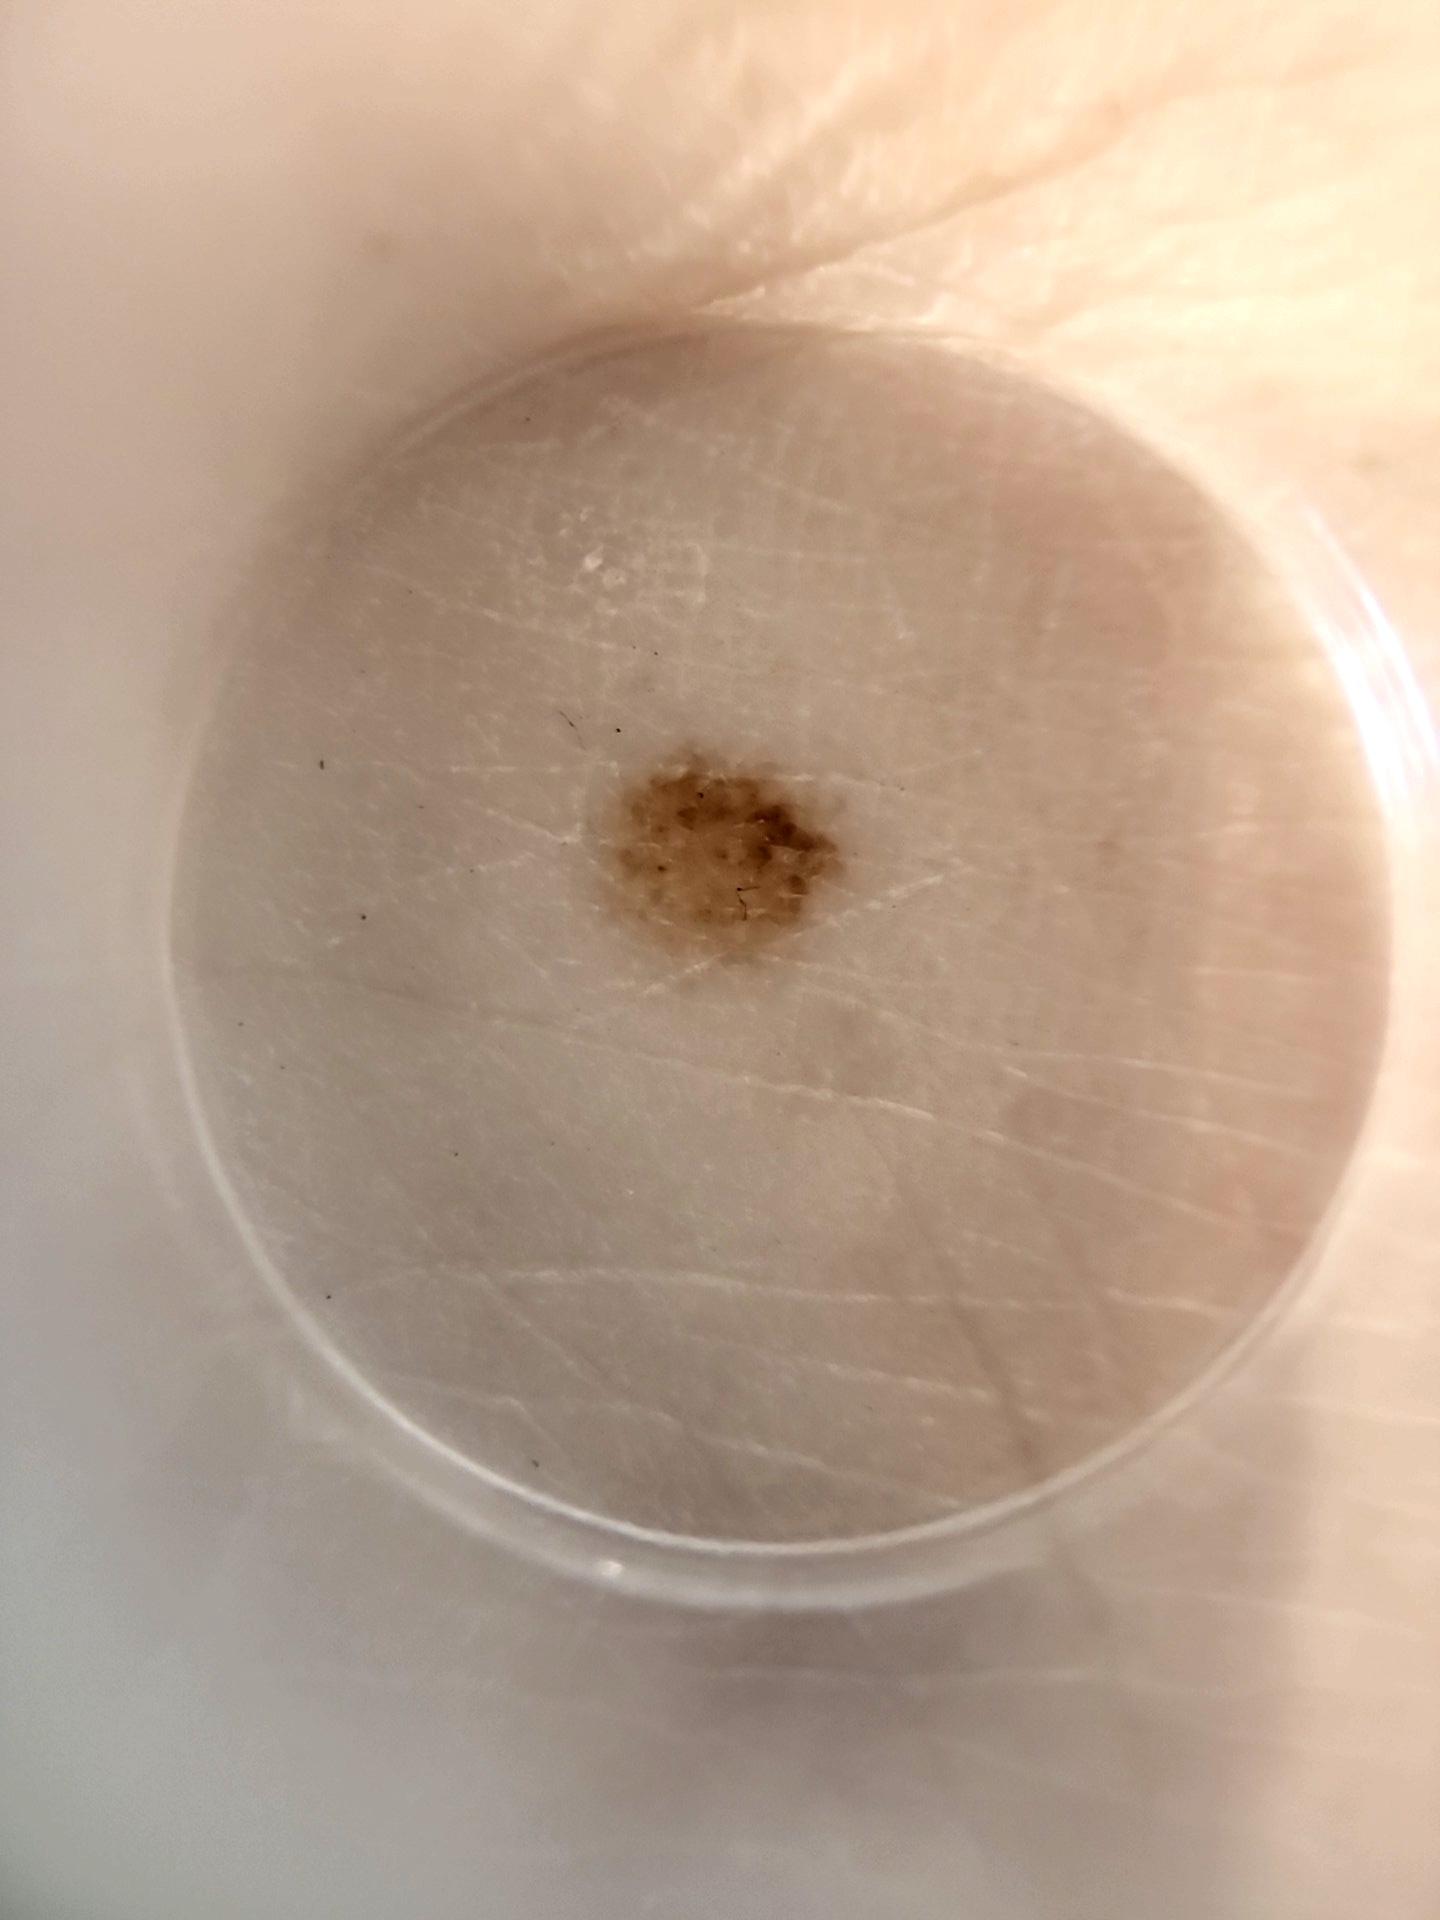

ISIC_8286416

IP_8159579

IL_3192179

image_type dermoscopic

lesion_id IL_3192179

patient_id IP_8159579